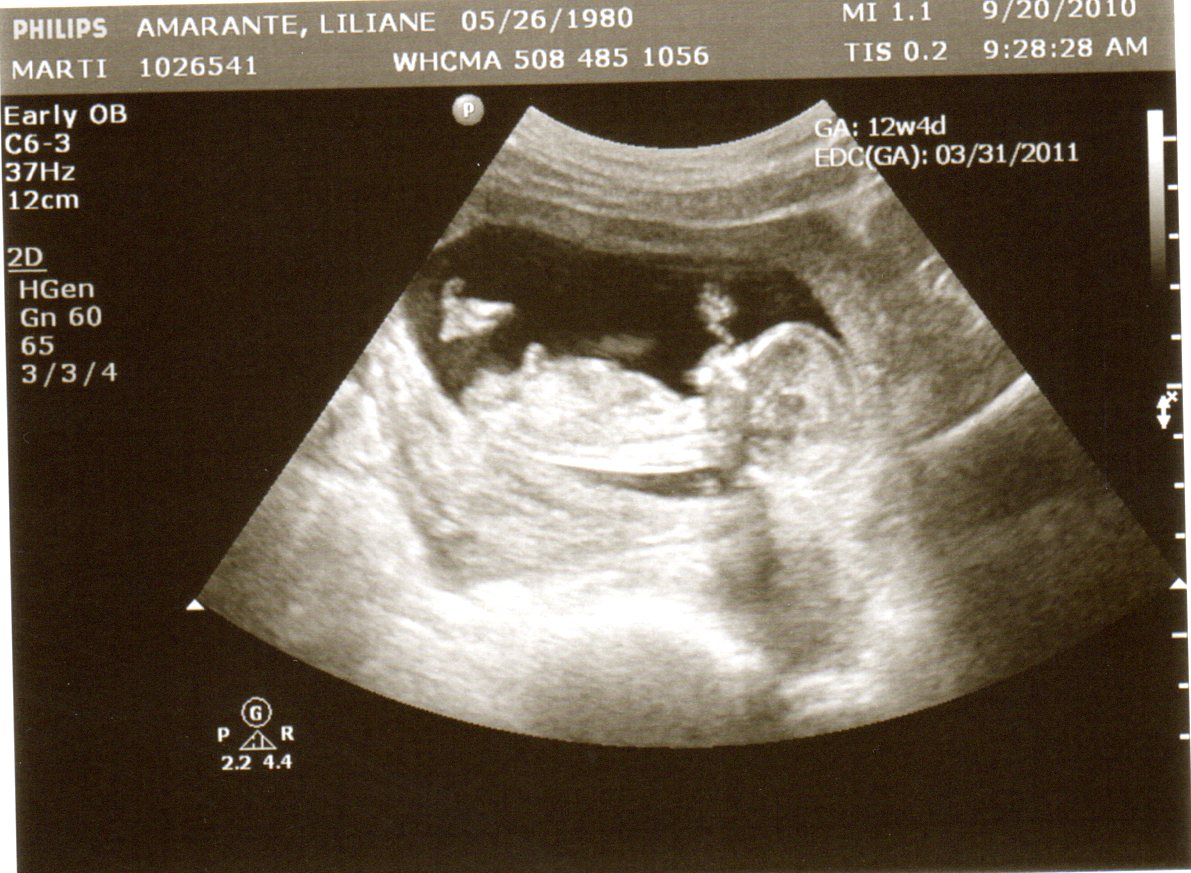

Hoje eu fui fazer mais um ultrassom e parece que tá tudo bem com o bebê.

Ele agora tá medindo 7,3cm e ficou se mexendo bastante: abria e fechava a boca, levantava e abaixava o braço, muito legal! Já deu pra ver os dedinhos, nariz ... fofo!

Agora eu tô com 12 semanas de gestação e parece que os enjôos tão começando a dar um tempo. Eu não engordei quase nada ainda (menos de um quilo), ou seja, ainda não passei dos 50kg. A minha barriga tá bem inchada, mas pra quem olha não dá pra perceber muito ainda. Logo mais eu posto fotos da barriga.